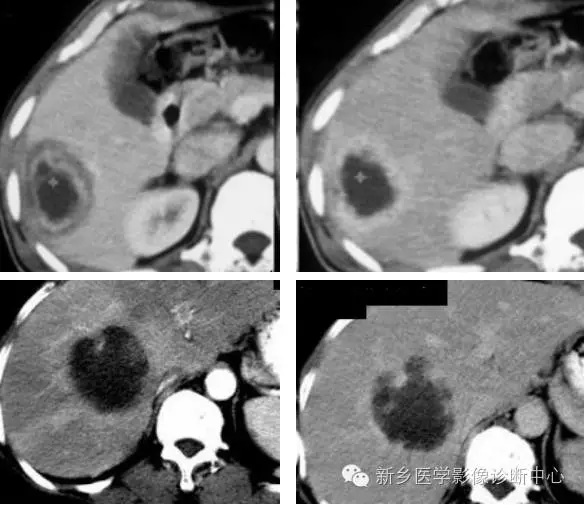

3、肝血管瘤

肝血管瘤在组织学上分为海绵状血管瘤、硬化性血管瘤、血管内皮细胞瘤和毛细血管瘤。是肝脏最常见的良性肿瘤。肝脏的血管瘤多数为海绵状血管瘤。多无临床症状。

病理表现:单发或多发,可位于肝包膜下,向外突出于肝表面,也可比较深在。肿瘤被覆结缔组织被膜,与周围肝组织分界清楚,由充满血液的血管囊腔构成,囊腔间有纤维性分隔。肿瘤可发生纤维化,钙化及血栓形成。

CT表现特点:病灶多为圆形或类圆形,边界清楚但无假包膜。平扫呈均匀低密度,增强扫描病灶边缘呈明显的不连续的结节状强化,强化区域进行性向中心扩展。延迟扫描病灶呈高密度充填。较大的病灶中心可见始终不充填。

血管瘤与其他富血供肿瘤的鉴别:①血管瘤的强化与血管相当。②血管瘤在延迟影像上呈持续强化。③血管瘤有周围结节样强化,其环内缘呈波浪状,而肝转移瘤其强化环内缘凹凸不平。④血管瘤增强后呈进行性持续性、向心性强化,无“周围洗脱”现象。